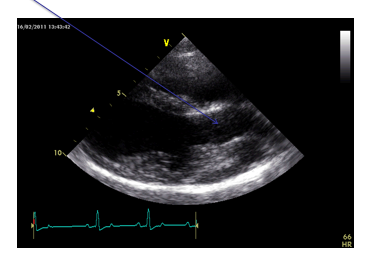

What view is this?

Right parasternal long axis 4 chamber